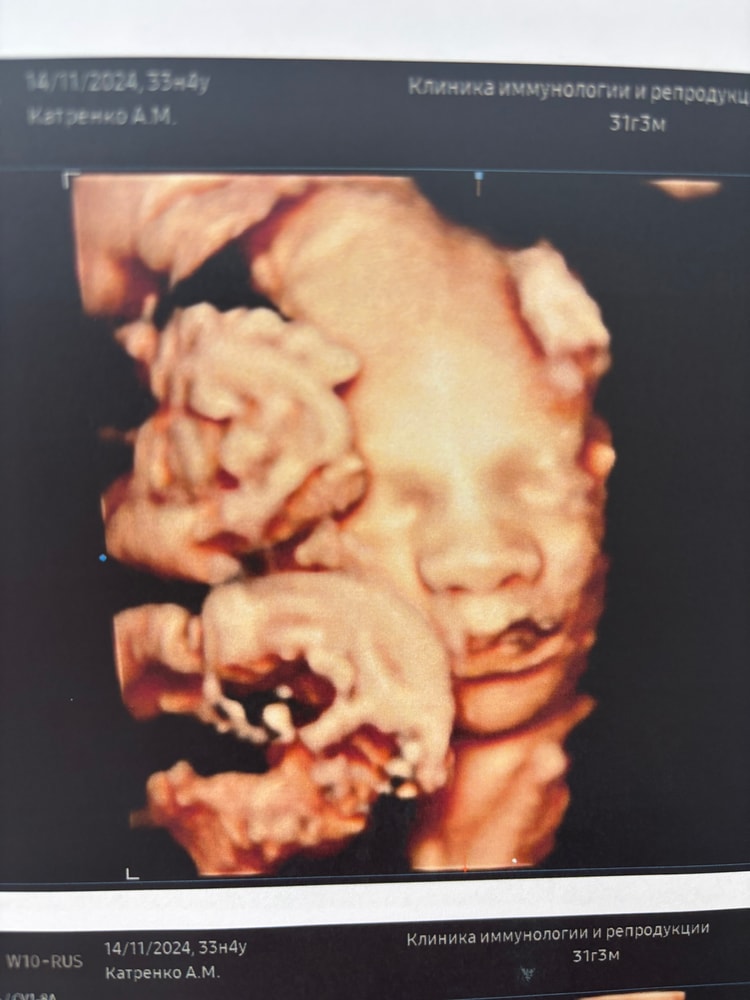

3D УЗИ в 33-34 недели.

Анна, моя двойня на 33 неделе. Все видно 👍🏻

Отличные фотки вышли,была в 31 неделю

Ольга, я читала , что лучше до 32 недель сделать, а потом хуже видно уже становится. Но видимо ,кому как повезет.